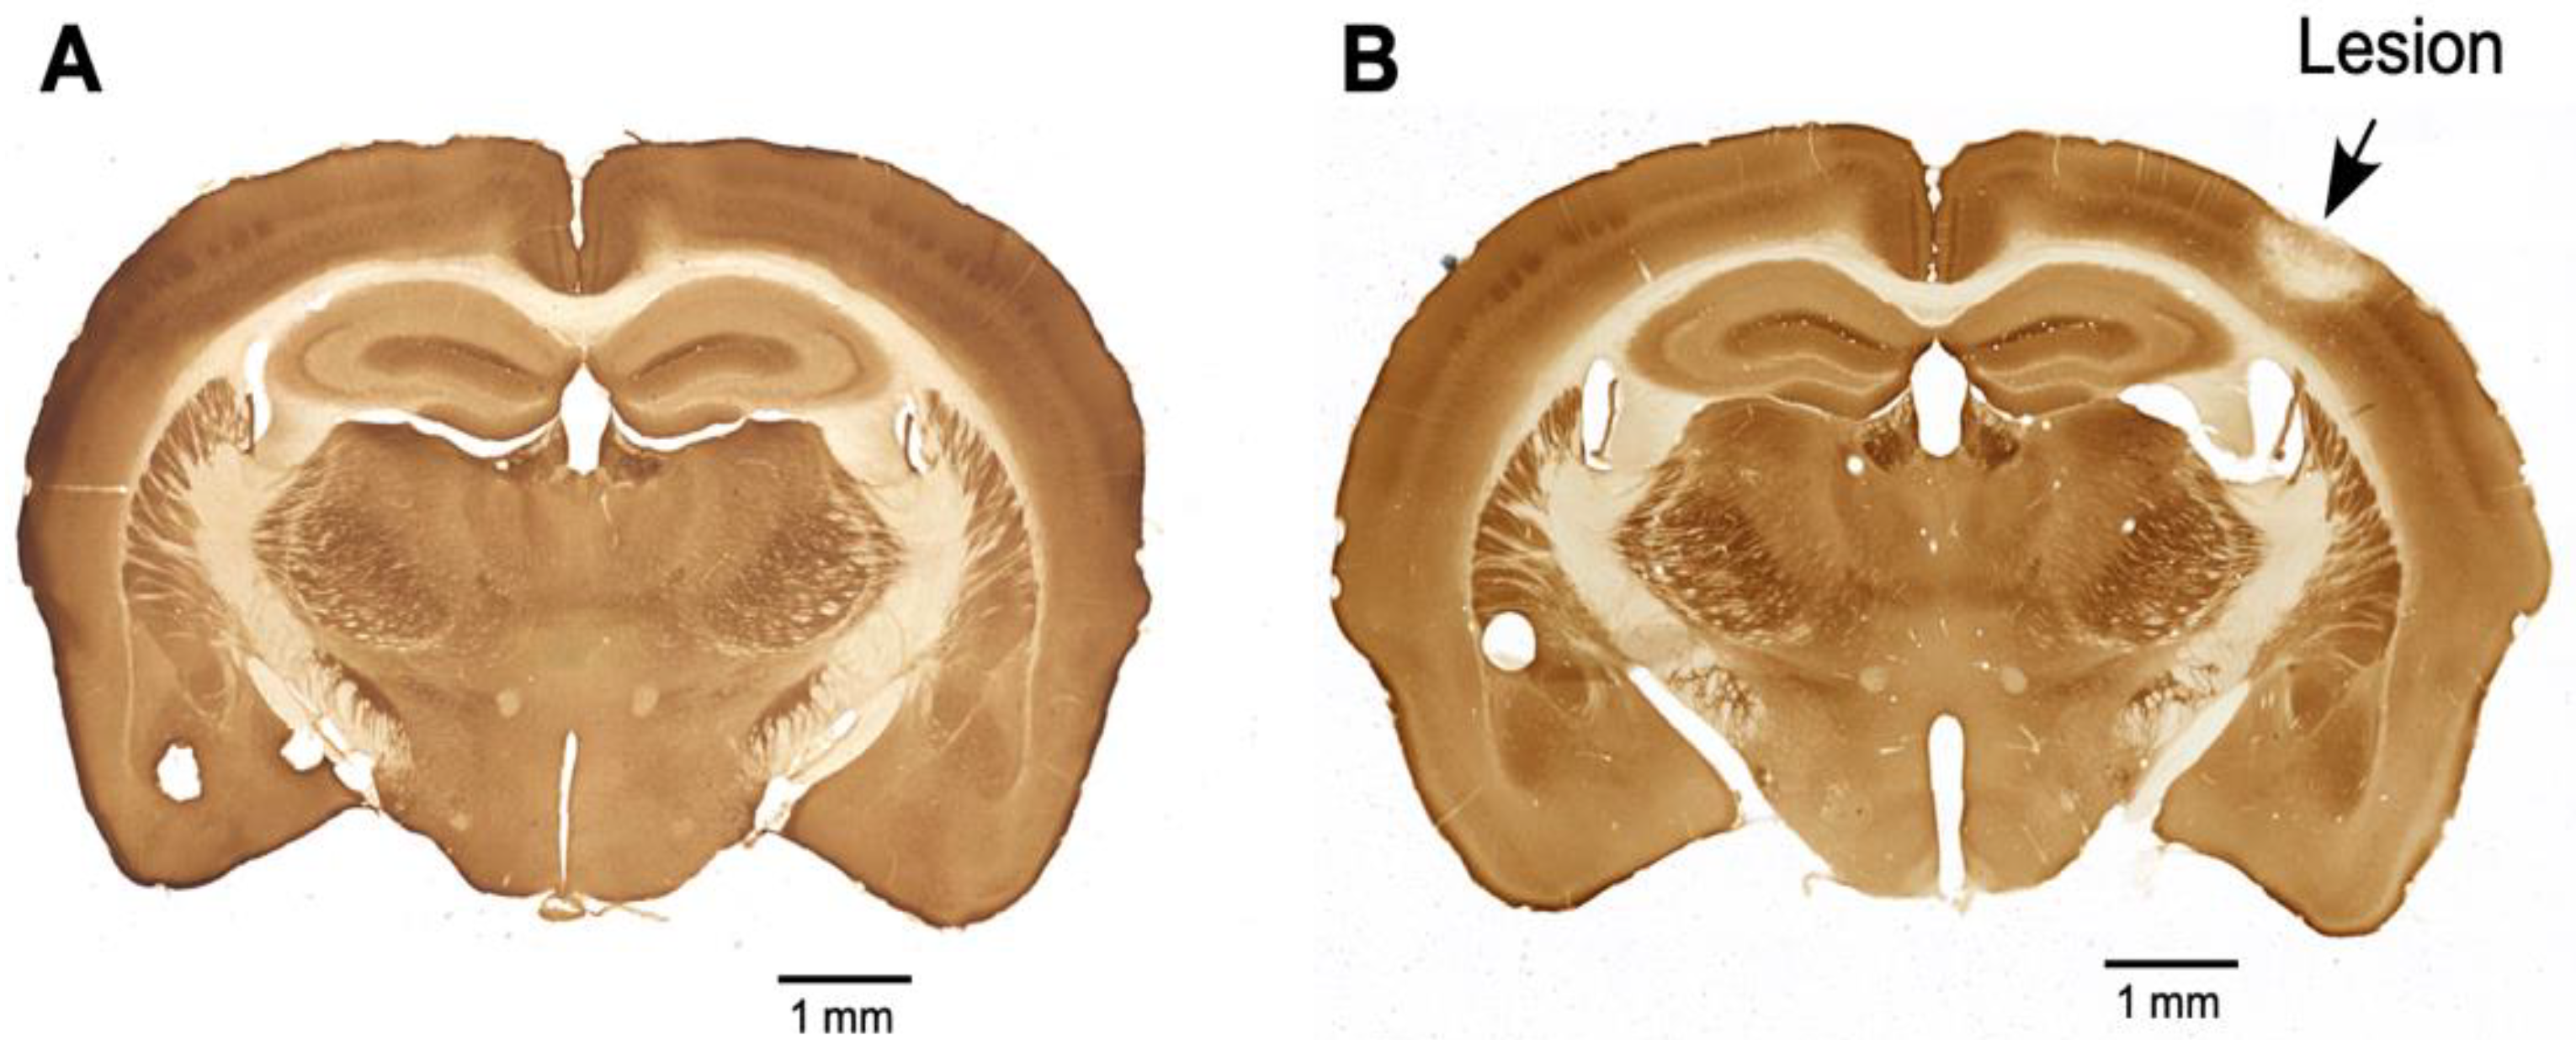

2.4. Cytochrome Oxidase Reaction

The four animals with sham control and the four animals with PTL were given saline for seven days post-lesion. On the eighth day, the animals were perfused transcardially with PBS (NaCl (80 gm), KCl (2 gm), Na2HPO4 (11.4 gm), and KH2PO4 (23.2 g) in 900 mL of water and then forming a volume of 1 L, pH-7.4) to clear the blood and then with 4% paraformaldehyde in PBS (PFA) to fix the tissues. The brains were removed and postfixed for 24 h in 10% sucrose in a PFA solution at 4 °C. The brains were cryoprotected by sequentially allowing them to sink in 20% sucrose in PBS, followed by 30% sucrose in PBS at 4 °C. The forebrain was cut into 30 µm thick sections on a sliding microtome. Every sixth section was reactive for cytochrome oxidase. The sections were washed three times with PBS at room temperature and then immersed in freshly prepared cytochrome oxidase staining solution (in 30 mL of 0.1 M phosphate buffer, sucrose (5 g), cytochrome C (Sigma, St. Louis, MO, USA; 25 mg), and DAB (Sigma; 20 mg) were dissolved, and the volume of solution was made up to 50 mL with phosphate buffer). The sections were incubated for 5 h at 37 °C. The sections were then washed twice with PBS, mounted on gelatin-coated glass slides, air dried, and coverslipped with DPX mounting medium. The sections were observed under a light microscope and imaged. Figure 1 shows sections from the brains of sham control animals (Figure 1A) and PTL animals (Figure 1B). In Figure 1B, the cortical region where the photothrombotic lesion was done appears pale, suggesting that cells in the area are dead, as indicated by the absence of cytochrome oxidase activity.

Figure 1.

Photomicrograph showing brain sections that were reacted for cytochrome oxidase from (A) a sham control mouse and (B) a PTL mouse. The lesioned area, indicated by the arrow, shows a region with inactive cells.